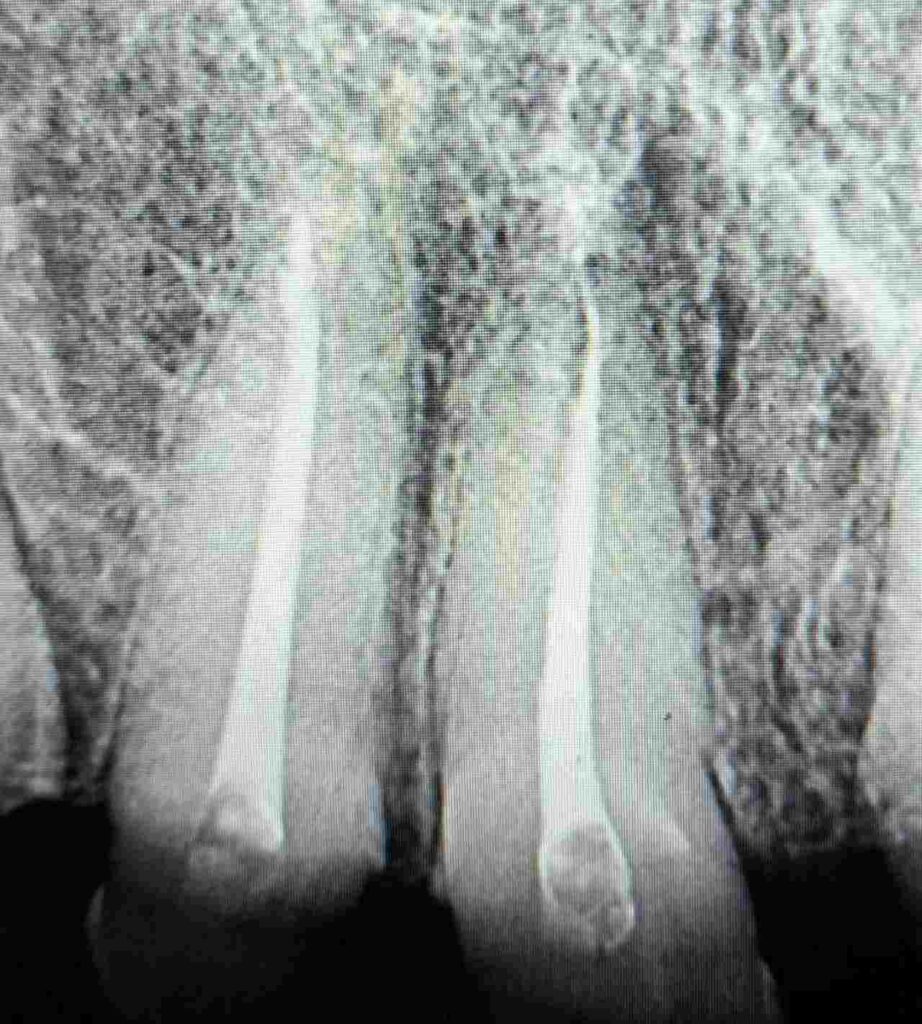

Tras la evaluación clínica y radiográfica detallada, se indicó tratamiento endodóntico en los dientes 11, 12, 21 y 22 con el objetivo de restablecer la salud del sistema de conductos radiculares y crear una base biológica sólida para la posterior rehabilitación protésica del sector anterior.

Durante todo el protocolo se realizaron irrigaciones activas con soluciones desinfectantes, garantizando la eliminación completa de detritos y microorganismos. Finalmente, se completó la obturación tridimensional del sistema radicular, logrando un sellado hermético confirmado por control radiográfico.

- Dientes: #11, #12, #21, #22

- Diagnóstico: Desgaste severo asociado a bruxismo crónico

- Desafío: Endodoncia múltiple simultánea para rehabilitación integral

- Obturación 3D y control radiográfico